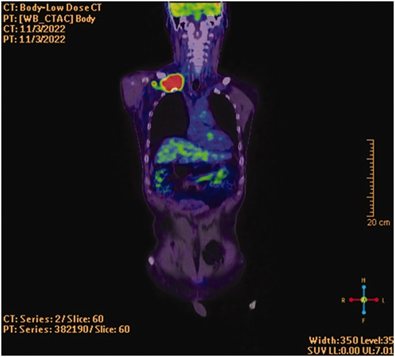

Do đau kéo dài không đáp ứng, bệnh nhân được chuyển khám ngoại lồng ngực và thực hiện CT ngực cùng PET/CT. Kết quả cho thấy một khối mô mềm lớn vùng trên đòn phải kèm hạch nách phải, nghi ngờ khối u ác tính hoặc viêm.

Sinh thiết dưới hướng dẫn siêu âm xác định ung thư biểu mô tế bào vảy di căn. Bệnh nhân được xạ trị giảm nhẹ vùng trên đòn và nách phải, đồng thời hóa trị. Sau điều trị, mức độ đau giảm còn 3/10 theo NRS, cải thiện đáng kể chất lượng cuộc sống.